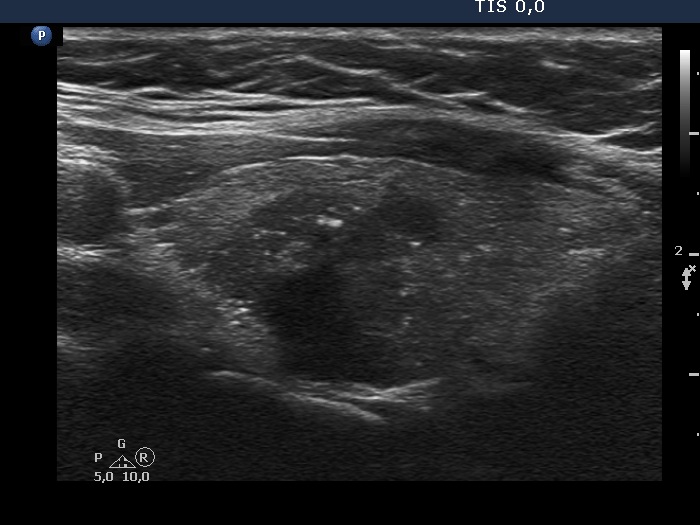

First examination (first two rows of images):

Clinical presentation: A 39-year-old woman went with her father to my consulting and she decided to request a thyroid examination. She has been treated with lithium for depression for more than 10 years. Two years after the initiation of antidepressant treatment hypothyroidism has developed. The patient was stopping the daily 50 microgram levothyroxine therapy one year ago because she felt no effect of the replacement treatment. Except for regular TSH determinations no other thyroid tests has been performed ever.

Palpation: both lobes were firm. There was a firmer nodule in the lateral part of the left lobe.

Laboratory tests: TSH 4.07 mIU/L, FT4 11.2 pM/L, aTPO 206 U/mL on daily 900 mg lithium.

Ultrasonography. The thyroid was minimally-moderately hypoechoic and presented pronounced fibrotic changes. The left lobe had several hypoechoic nodules having cystic areas and numerous microcalcifications. Isolated microcalcifications were found in large numbers outside the nodules. The tumor showed irregularly increased intranodular vascularization.

Cytology. Papillary cancer.

Histopathology. Multifocal papillary cancer in the left lobe. The diameter of the largest focus was 20 mm. There were numerous smaller tumor foci, less than 2 mm in diameter.

Comments.

The ultrasound presentation is suspicious of invasive spread.

It is worth comparing the presentations of fibrosis in the right lobe and that of the microcalcifications outside the nodule in the left lobe.